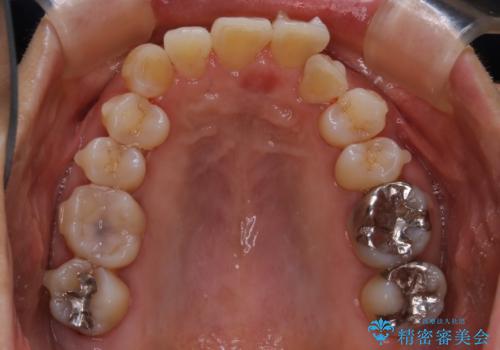

- 上下の歯のがたつきと、噛み合わせが深いことを気にされてご相談にいらした方です。噛み合わせに参加していない歯を抜歯してインビザラインにて治療を行いました。

一般的に噛み合わせの深い方へのインビザライン治療は適応が難しいとされていますが、今回は噛む力を上手にコントロールできたことと、内側に入り込んでいた前歯の角度を調整したことで下の歯がしっかり見えるようになりました。短期間で劇的に見た目が改善し、大変喜んでいただけました。